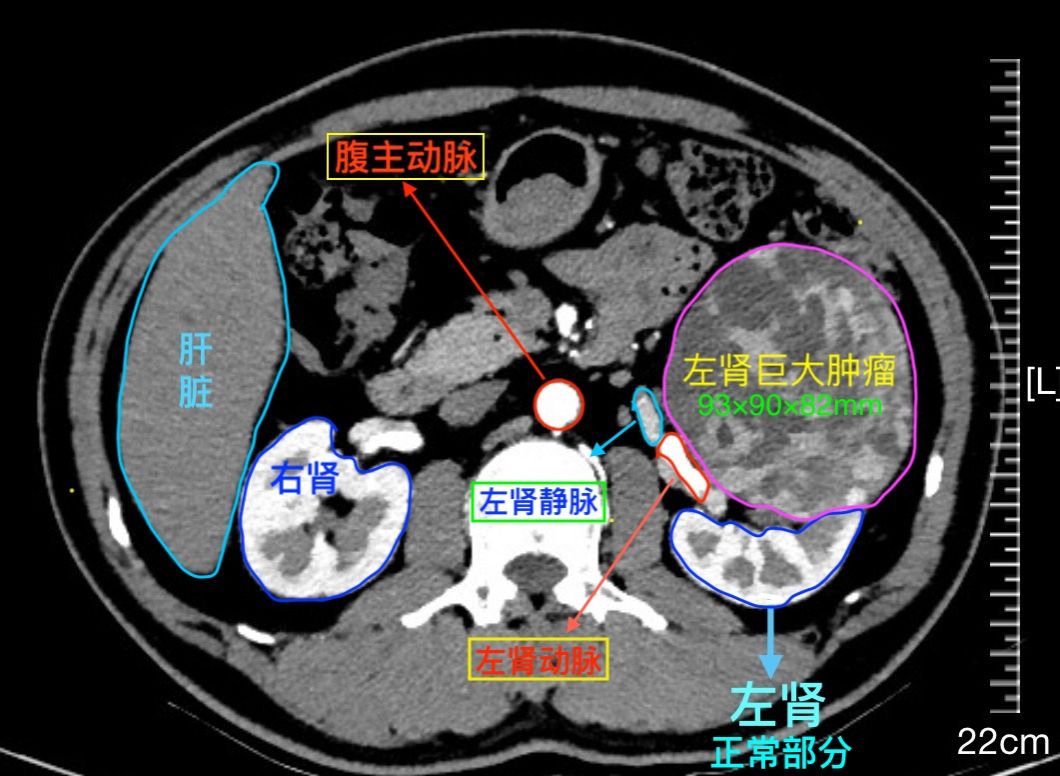

患者文先生在一次常规体检中,意外发现左肾存在一个巨大占位。进一步的增强CT检查结果令人倒吸一口凉气:一个大小约93×82×90mm的类圆形肿瘤从肾脏突出,位置极其凶险,紧贴着肾门部的大血管和集合系统。经专业评估,该肿瘤R.E.N.A.L评分高达11分,属于“高度复杂”级别。

(术前CT影像清晰显示左肾巨大肿瘤,如一颗“定时炸弹”)